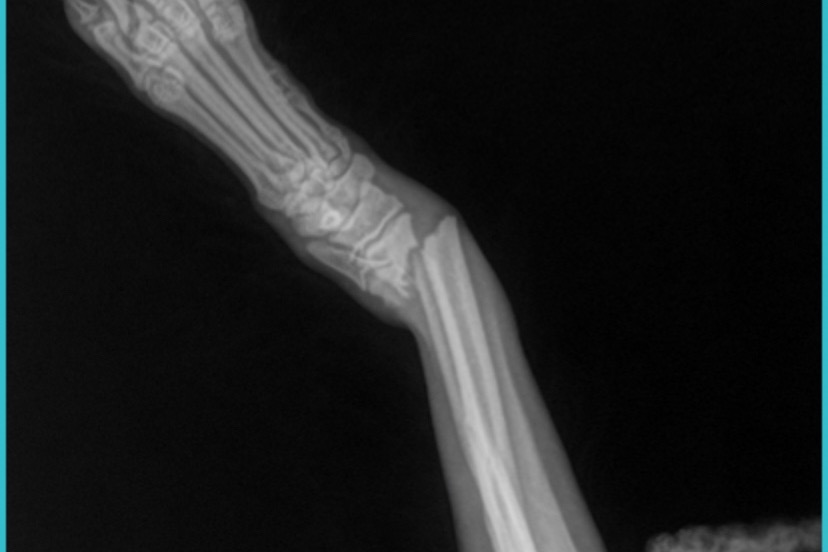

My puppy had an accident Friday and broke her tiny arm in two places. She needs pins put in by an orthopedic specialist. She is currently in a temporary bandage, but needs surgery to be able to walk and fully function again. We appreciate any donation for Kirikiri.